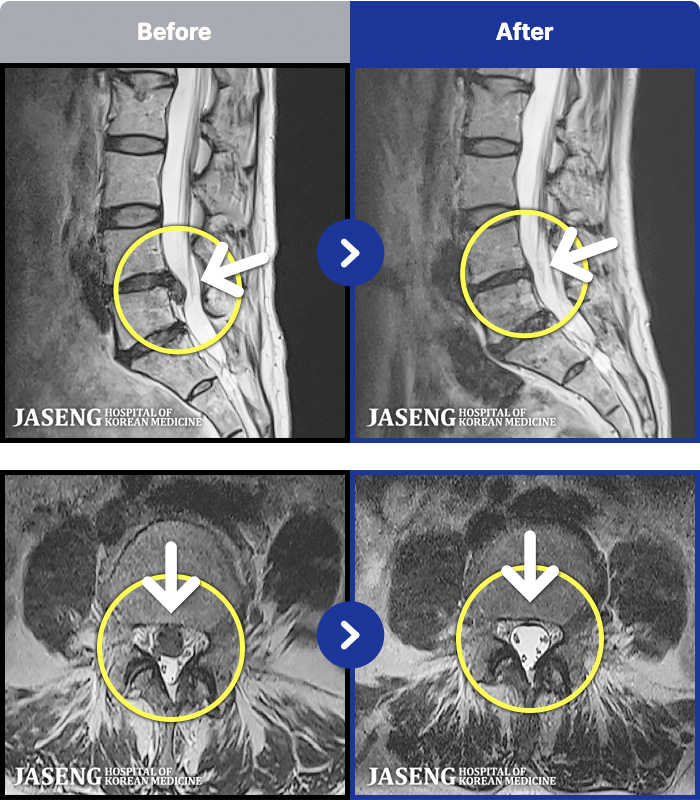

[뱸] 19.11.28~25.05.06